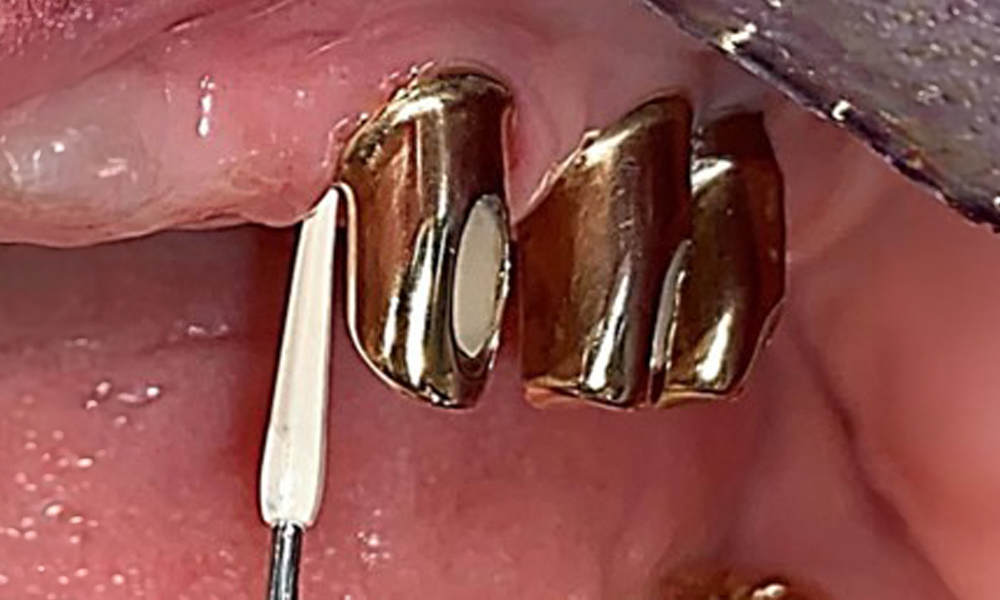

На пациентката е поставена комбинирана подвижна горночелюстна телескопична протеза преди повече от 25 години (фиг. 1, фиг. 2, фиг. 3) и тя е много доволна от протезите си. Пациентката има адекватна фиксирана протеза за долната челюст (фиг. 4).

Денталните открития са следните: Комбинирани снемаеми протези на импланти и телескопични протези, поддържани от зъби, на импланти 15, 13, 21, 23, 24, 25 и зъб 11 (фиг. 1, фиг. 2, фиг. 3). Пациентът е снабден с фиксирана долночелюстна протеза. Над зъби 37-34 и 45-47 бяха налични адекватни мостове (фиг. 4), краищата на коронките бяха интактни и нямаше активен кариес. Върху зъб 43 имаше композитна пломба с маргинална празнина. Имаше рецесия на долната гингива, която разкриваше от 1 до 3 mm от кореновата повърхност. Това се отнася и за 11.

Специално за телескопичните протези се препоръчва еднократна четка (фиг. 8), а пациентът трябва да бъде посъветван за подходящия размер на интерденталната четка (фиг. 9). Пациентът изпълнява тези препоръки за интраорална хигиена у дома в продължение на много години и беше насърчен да продължи по време на професионалната профилактична среща с денталния лекар.